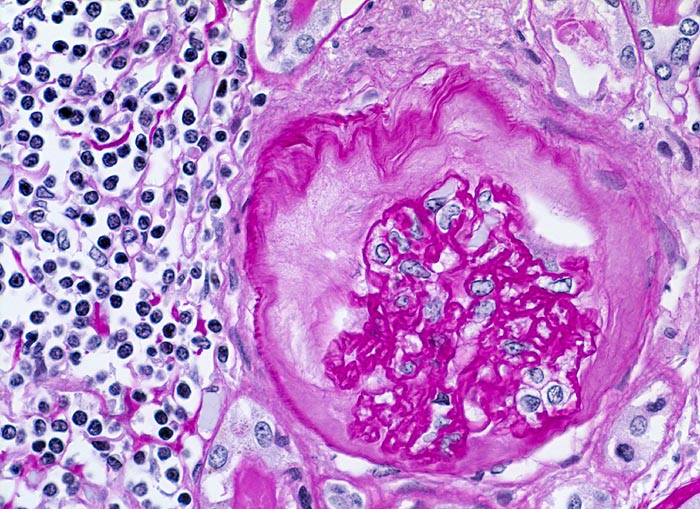

chronische Pyelonephritis

Glomerulum mit vollständig kollabierten Kapillarschlingen. Die Kapselbasalmembran ist aufgesplittert und verbreitert. Interstitielles überwiegend lymphozytäres Entzündungsinfiltrat mit Beimischung von Histiozyten.

Makroskopisch ist die Nierenoberfläche grobhöckrig deformiert durch zahlreiche Narben mit teils rotem, teils weissem Grund. Beide Nieren sind verkleinert (Gewicht beider Nieren zusammen 180g). Das leicht ausgeweitete und gerötete Nierenbecken enthält mehrere kleine harte zackig begrenzte grauschwarze Kalziumoxalatsteine.

Nephrolithiasis und wiederholte akute pyelonephritische Schübe beidseits. Arterielle Hypertonie.